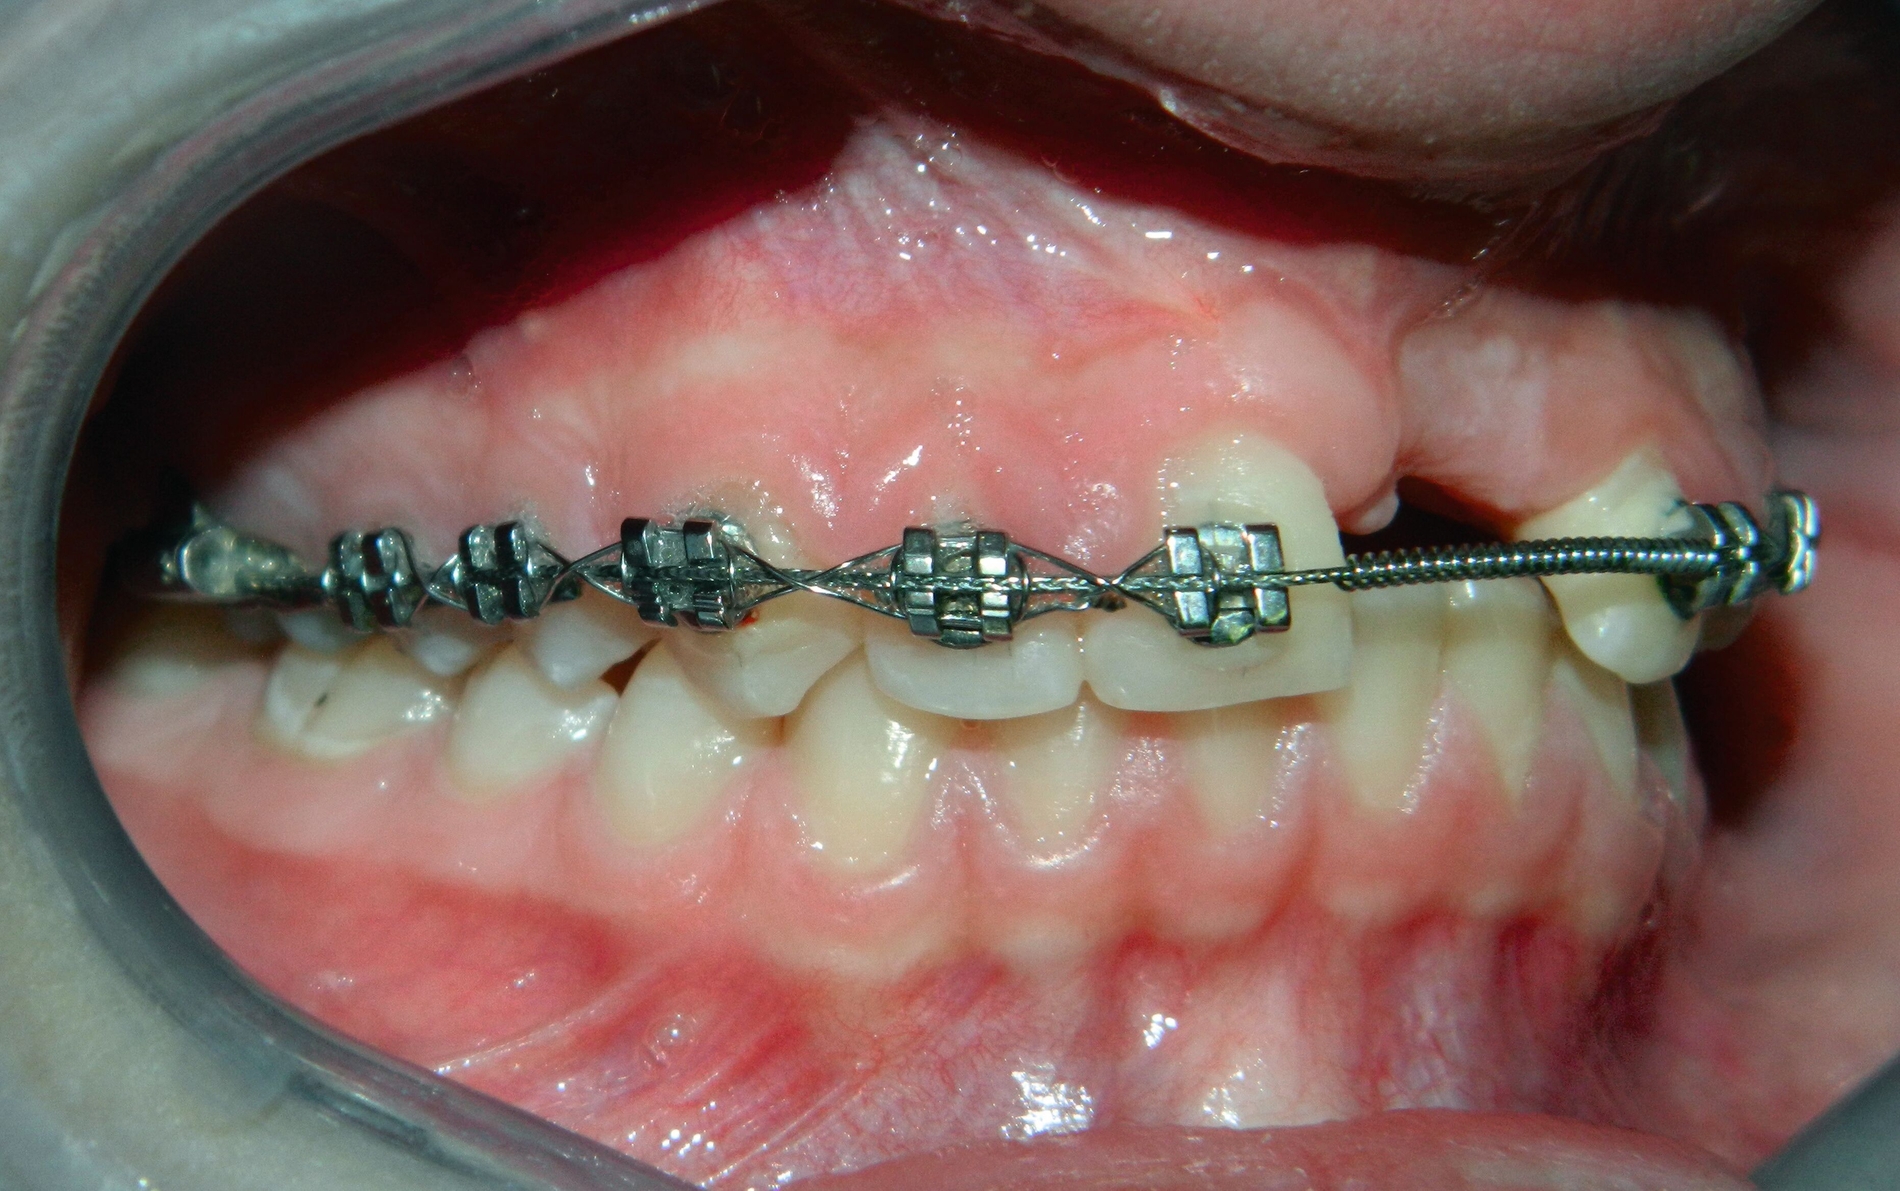

Im Februar 2019 wurde die kieferorthopädische Klinik von der Erstautorin übernommen. Bei der Auswertung der vorgefundenen Daten der Patientin wurde festgestellt, dass der linke obere zentrale Schneidezahn vor sechs Monaten extrahiert worden war. Die festsitzende Apparatur war im Oberkiefer bereits eingegliedert. Die Druckfeder zwischen Zahn 11 und 22 diente zur Lückenöffnung für den späteren prothetischen Ersatz des Zahnes 21. Auch auf den persistierenden linken Milcheckzahn war ein Bracket geklebt. Die Okklusion im Bereich der ersten Molaren war rechts und links neutral (Abbildung 2).